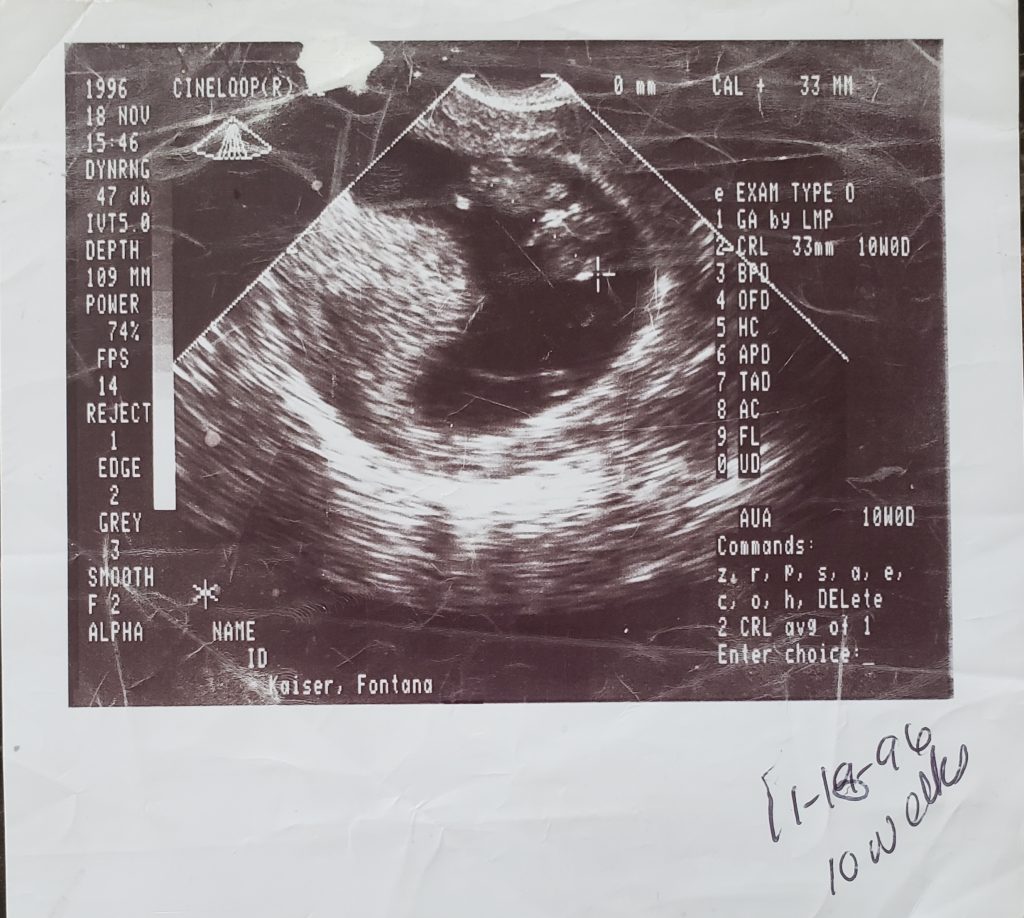

On March 10, 1997, former San Bernardino County Probation Officer Rodney Patrick McNeal brutally murdered his wife, 39-year-old Debra Marie Crow McNeal, and unborn child Samara, in Highland, California.

Baby Samara McNeal

During his incarceration, Mr. McNeal has made claims on a couple of occasions that Debra was after his money. This statement is not true as Shantel stated that her six-month-pregnant mother was left nearly penniless by Mr. McNeal when he drained their shared bank accounts more than once.